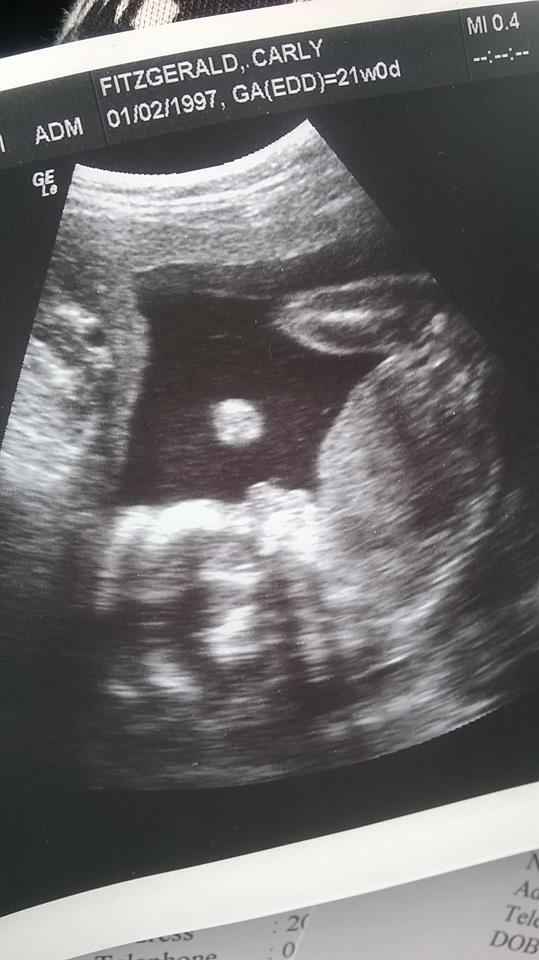

Hi everyone just wanted to know if you think my baby is a boy or girl , I am 21 weeks and was told it was a girl but there not always 100 % really hope its a girl!!

Attachment 26092

No but the woman said she could see 3 lines